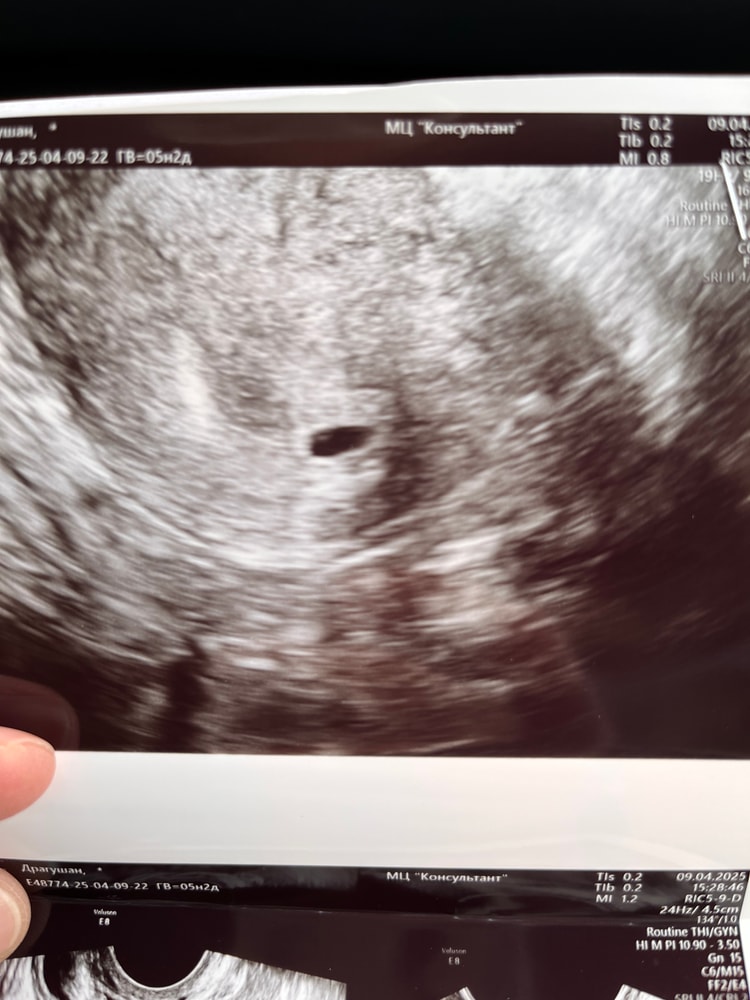

Плохое плодное яйцо